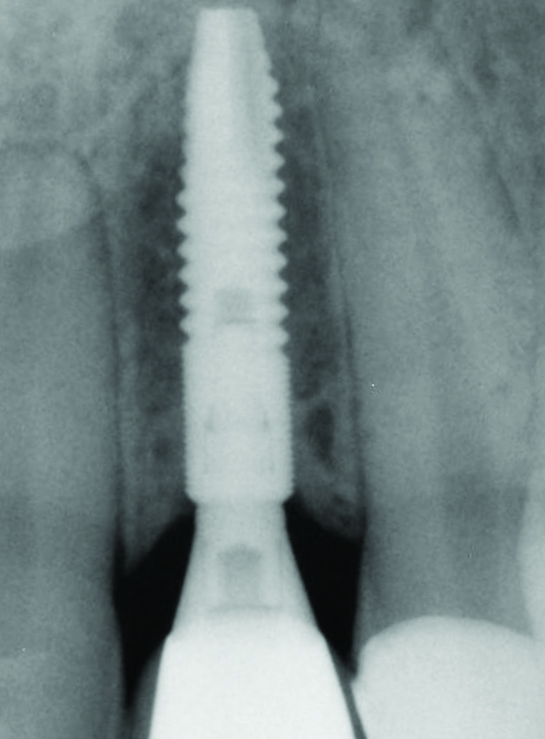

Fig 28. Radiograph on the day of surgery: Implant placement and provisional restoration. Note that the implants are subosseous, as their position is defined by the desired facial free gingival margin position.

Figure 28

Fig 29. One-year radiograph of the definitive restorations on the implants Nos. 8 and 9. Note the crestal bone stability compared to the radiograph taken on the day of surgery in Figure 28.

Figure 29

In the final case, adjacent implants were placed in healed sites No. 8 and No. 9 and provisionalized at the time of surgery (Figure 27 and Figure 28). This case illustrates the effect of platform switching on bone and gingival tissue stability, as well as recognizing that appropriate diameter and spacing is important to maintain ideal ridge contour. The gingival tissue anatomy between implants is characteristically shorter than papilla form between adjacent teeth, and, as a consequence, it is important to incorporate implant designs and procedures that minimize bone-level changes and associated soft-tissue recession. The depth of implant placement was subcrestal relative to the ridge crest, based on the future desired free gingival tissue level, while allowing prosthetic running room. The studies of Barros et al and Veis et al noted that implants positioned subcrestally (as seen in Figure 29) showed better crestal bone preservation than those placed equicrestally or supracrestally.28,29 The implant design used in this case achieves excellent primary stability. Along with the optimal 3-dimensional positioning of the implants and, specifically, the subcrestal placement, as well as the immediate provisionalization protocol, these concepts and implants have contributed to a pleasing esthetic outcome, as seen in Figure 30.